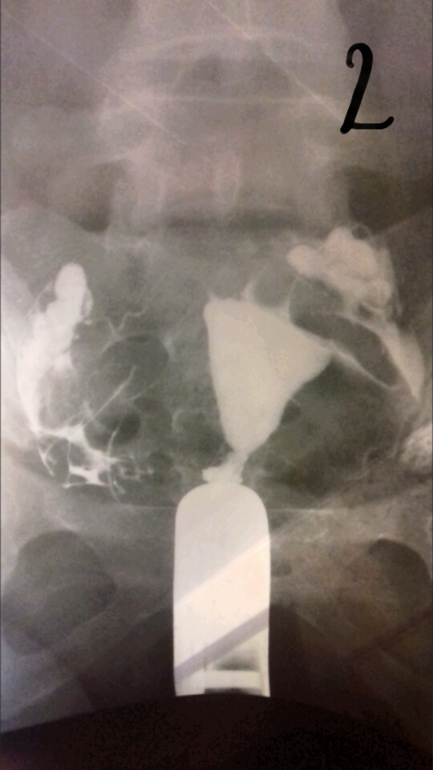

ГСГ помогите расшифровать.

ГСГ, ЭХО, МСГ, ФертилоскопияВсем привет. Кто понимает в снимках. Сделала гсг. На третьем сказали жидкость вышла, но как-то долго она выходила и спайки видно, поставили эндометриоз и спаечный процесс в брюшной полости. Беременность не наступает и стимуляции были. В 2006 году было кесарево и в 2012 прижигали эррозию ш/м, больше ничего.